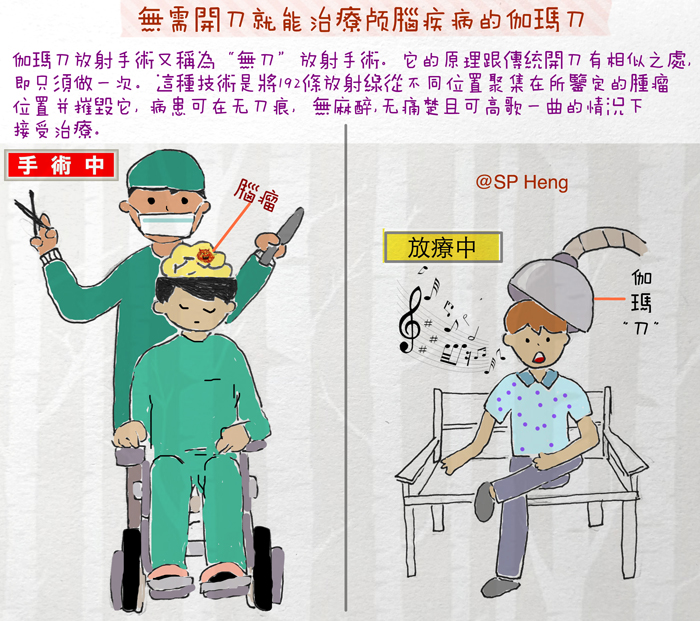

伽马刀常被形容为“隔山打牛”,意指能隔着颅骨以高能射线精准击中肿瘤,同时保护周边组织。治疗无需开颅、麻醉或住院,几乎无痛。虽然精准安全、疗效佳,但仍可能引起暂时性放射性坏死或掉发。总的来说,伽马刀属辅助疗法,应与手术相辅相成。

谈到伽玛刀,最常听到的一句形容词就是“隔山打牛”,因为伽玛刀是一种精确的非侵入式放射治疗法,利用高能量射线,配合立体定位系统,不用开颅,不必见血,就能治疗肿瘤。

伽玛刀是一种放射治疗,众所周知,放射线可以穿透人体,高能量的放射线能杀死癌细胞,但同时也会伤害正常细胞。伽玛刀以钴-60(Cobalt-60,简称Co-60)作为放射线的射源,192个单点射束排成一个半圆形的阵列,再把192个单点射束的能量聚焦在一处。单点聚焦的概念,意味着每个射束的能量都很低,但位于焦点处的能量却极高,如此一来,就能使用大剂量的放射线瞄准和治疗脑肿瘤,同时,将邻近脑组织的伤害降到最低。

伽玛刀并没有真正用刀,“刀”指的是192个放射射束、发挥宛如手术刀般精准的效果,故命名为伽玛刀。

伽玛刀放射手术的原理,是先用磁力共振造影(MRI)及立体定位系统,精确地找出肿瘤的三度空间座标,再用特制头架(frame)或面罩(mask),把病人的头颅依座标值固定于伽玛刀仪器内,确定头部与仪器不会因为移位而产生误差,进而确保放射线准确聚焦在病灶上,而不伤及周边的脑结构。

盛晓峰指出,伽玛刀的特点是精确、与开颅手术相比更安全,并且疗效良好,“不需要剃发,也不需要开颅和麻醉,几乎无痛,治疗后不必留院。”